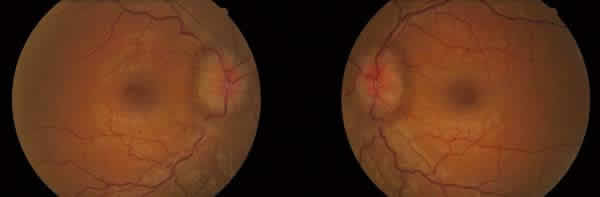

A la exploración presentaba una AV de 0,8 en AO. El polo anterior y la PIO se encontraban dentro de la normalidad. El FO presentaba un edema de papila bilateral, con exudación lipídica en AO y hemorragias peripapilares en el ojo derecho (OD) (fig. 4). La AFG mostraba fuga de contraste alrededor del nervio óptico en AO (fig. 5). En la perimetría automatizada (Humphrey 24.2) se observó una retracción concéntrica del campo visual bilateral, más acentuado en el ojo izquierdo (OI) (fig. 6).

Fig. 4: En la funduscopia se observa un edema de papila

bilateral asimétrico, con exudación lipídica peripapilar en AO y hemorragias en

OD.

En el segundo caso, la paciente acudió a urgencias por presentar visión borrosa. El hecho de tener un edema de papila bilateral aunque con evidente componente hemorrágico debe hacer pensar en un principio en un origen central, pero todas las exploraciones, incluidas pruebas de imagen, resultaron negativas por lo que se descartó dicha causa. Ante esta situación, debe pensarse en patología sistémica o en etiología local y bilateral, algo que realmente no es muy frecuente. Se realizó el diagnóstico diferencial entre etiología compresiva (tumor orbitario, enfermedad tiroidea, fístula carótido-cavernosa), etiología vascular inflamatoria (sarcoidosis, sífilis, lupus eritematoso sistémico, Behçet), síndromes de hiperviscosidad sanguínea (leucemia, linfoma, mieloma múltiple, policitemia, anemia de células falciformes, disproteinemias). Como todas las pruebas realizadas fueron negativas con excepción de los altos títulos de anticoagulante lúpico, se diagnosticó a la paciente de SAF primario, pues no tenía ninguna otra patología asociada. En estos casos los AAF, producen un estado de hipercoagulabilidad, que en nuestra paciente indujo oclusiones10-12 a nivel de la microcirculación de ambos nervios ópticos, produciendo una papiloflebitis bilateral como la que observamos en las imágenes (fig. 4), se observa edema de papila bilateral asociado a un gran componente hemorrágico peripapilar y exudación lipídica.